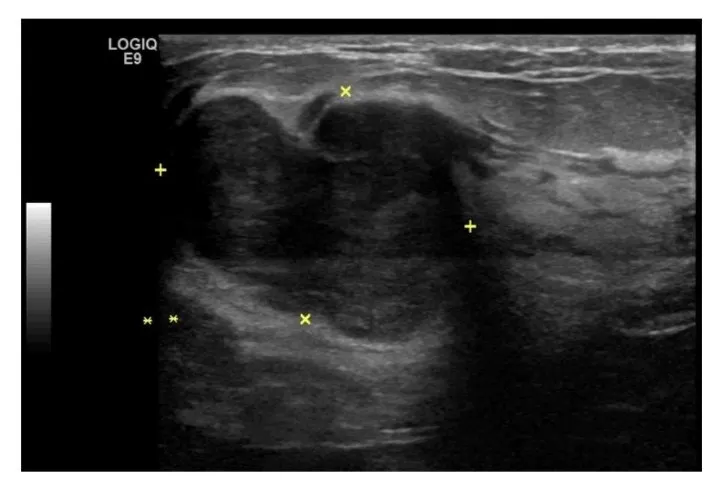

30 歲的許小姐日前摸到左側乳房有明顯腫塊,且短期內快速變大,雖然沒有疼痛,但明顯的改變卻造成心理壓力,遂主動前往就醫。經乳房超音波與粗針切片檢查發現,許女士乳房有一約 3 公分大的葉狀瘤及 2 顆小腫瘤,考量病灶接近乳頭且其他小腫瘤也無法排除是否為葉狀瘤,經充分討論後,陳昱天醫師執行內視鏡輔助微創乳房全切除手術合併重建,病理結果確認 3 顆腫瘤皆為良性葉狀瘤,所幸手術順利、腫瘤完全切除,後續追蹤未見復發。

術前超音波可見有一約3公分大的腫瘤。(4個黃色+字標記處)。(台北慈濟醫院提供)